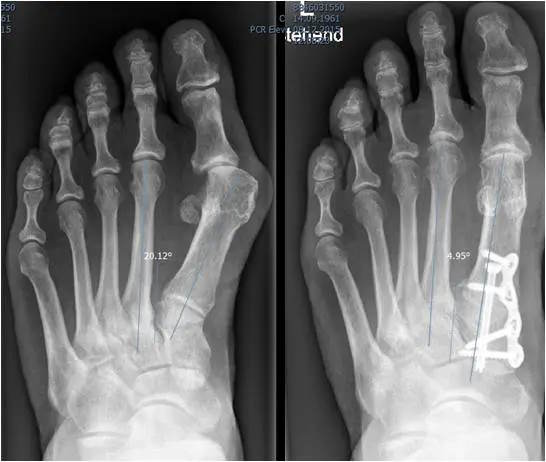

Die bildgebende Diagnostik umfasst ein Röntgenbild im dorso-plantaren Strahlengang des belasteten Fußes. Auf der dorso-plantaren belasteten Aufnahme können der Winkel zwischen dem Metatarsale I und II (Intermetatarsal Winkel) und der Winkel zwischen Metatarsale und Großzehe (HV Winkel) bestimmt werden. Zudem können die Kongruenz des Großzehengrundgelenkes bzw. die Stellung der Sesambeine beurteilt werden. Weitere Aufnahmen sind in der Regel nicht erforderlich. Schrägaufnahmen oder schnittbildgebende Verfahren wie eine MRT oder CT Untersuchung bleiben besonderen Fragestellungen vorbehalten.

Osteotomien bezeichnen die Durchtrennungen und Umstellungen von Knochen. Sie können an der Basis der Großzehe, am zehenseitigen (distalen) Mittelfußknochen am Schaft des Mittelfußknochens oder an der Basis des Mittelfußknochens einzeln oder in Kombination durchgeführt werden. Die Verschiebung und Fixation des Knochens in korrigierter Stellung soll eine dauerhaften Umstellung erzielen. Eine der häufigsten Osteotomien ist die Chevron- und die Akin- Osteotomie. Osteotomien werden häufig mit Weichteileingriffen kombiniert.

Eine übermäßige Beweglichkeit im ersten Mittelfußgelenk (TMT-I Gelenk) bei gleichzeitiger Achsabweichung des Mittelfußknochens kann mittels einer TMT I-Gelenk oder sog. Lapidus Arthrodese behandelt werden. Die TMT I Arthrodese wird auch häufig bei sehr schweren Hallux valgus Stadien angewendet. Sie kann mit anderen Techniken, wie Osteotomien oder Weichteileingriffen kombiniert werden.